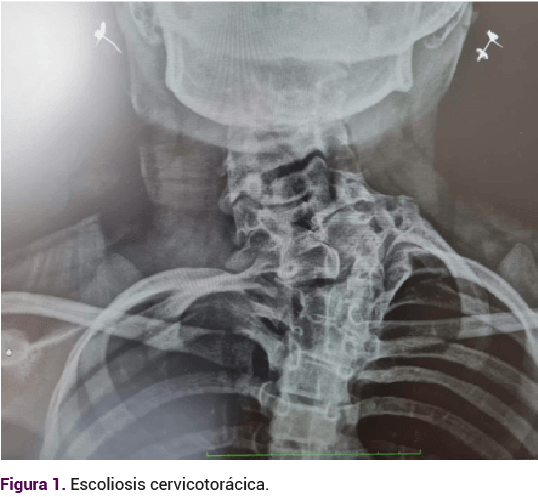

Adolescente de 14 años, que acudió a consulta debido a la amenorrea primaria. Antecedentes relevantes: embarazo conseguido mediante técnicas de fertilización in vitro. Durante la etapa prenatal se le diagnosticó riñón en herradura. En los primeros días de nacida el ultrasonido reportó: ectasia pielocalicial y requirió cateterismo. En la exploración neonatal se apreciaron fisuras palpebrales antimongoloides, paladar ojival, epicanto interno, puente nasal amplio y genitales externos femeninos. El cariotipo 46XX, sin alteraciones estructurales. La valoración audiológica fue normal. A los 8 y 10 años requirió cateterismo ureteral por síntomas urológicos. La radiografía de columna cervicotorácica por escoliosis, tomada a los 12 años, reportó una fusión costal posterior derecha del primero al cuarto arco, hemivértebras C6, C7 y T1, además de fusión de los cuerpos vertebrales de C2 y C3. Ausencia de apófisis espinosas de C5 hasta C7. Figuras 1 y 2

Alteraciones esqueléticas. La afección más común es la escoliosis en la columna cervical (17%), pero suelen ser diversas, como agenesia de toda la vértebra, hemivértebras segmentadas, fusión vertebral o vértebra en bloque (anomalía de Klippel-Feil) 4%.4,23,24